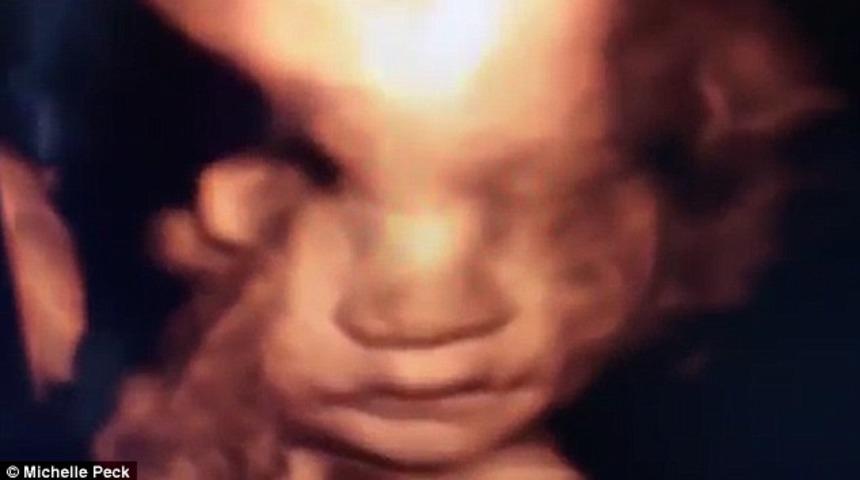

Nisan aylarında bebeklerini kucaklarına almaya hazırlanan anne Michelle ve baba Andrew, hamilelik boyunca yapılan taramalar esnasında bebeklerinin yüzünü göremediğini, bu yüzden daha detaylı olan 4 boyutlu ultrasonu denemeye karar vediklerini söylediler.

Taramaya girmeden önce dolu bir kase dondurma yiyen Michelle, '' hamileliğim boyunca onun yüzünü göremedik. Ya koluyla yüzünü kapatıyor ya da poposunu bize dönüyordu. Bu kez daha detaylı bakmak istedik. Ve girmeden önce de bir kase dondurma yedim. Ultrasonda bakarken oldukça hareketli, içi içine sığmayan bir bebekle karşı karşıyaydık.

Ancak sondaki sürprizi hiç beklemiyorduk. Bebeğimiz bize gülümsüyordu. Bu inanılmaz bir andı'' diye konuşuyor.